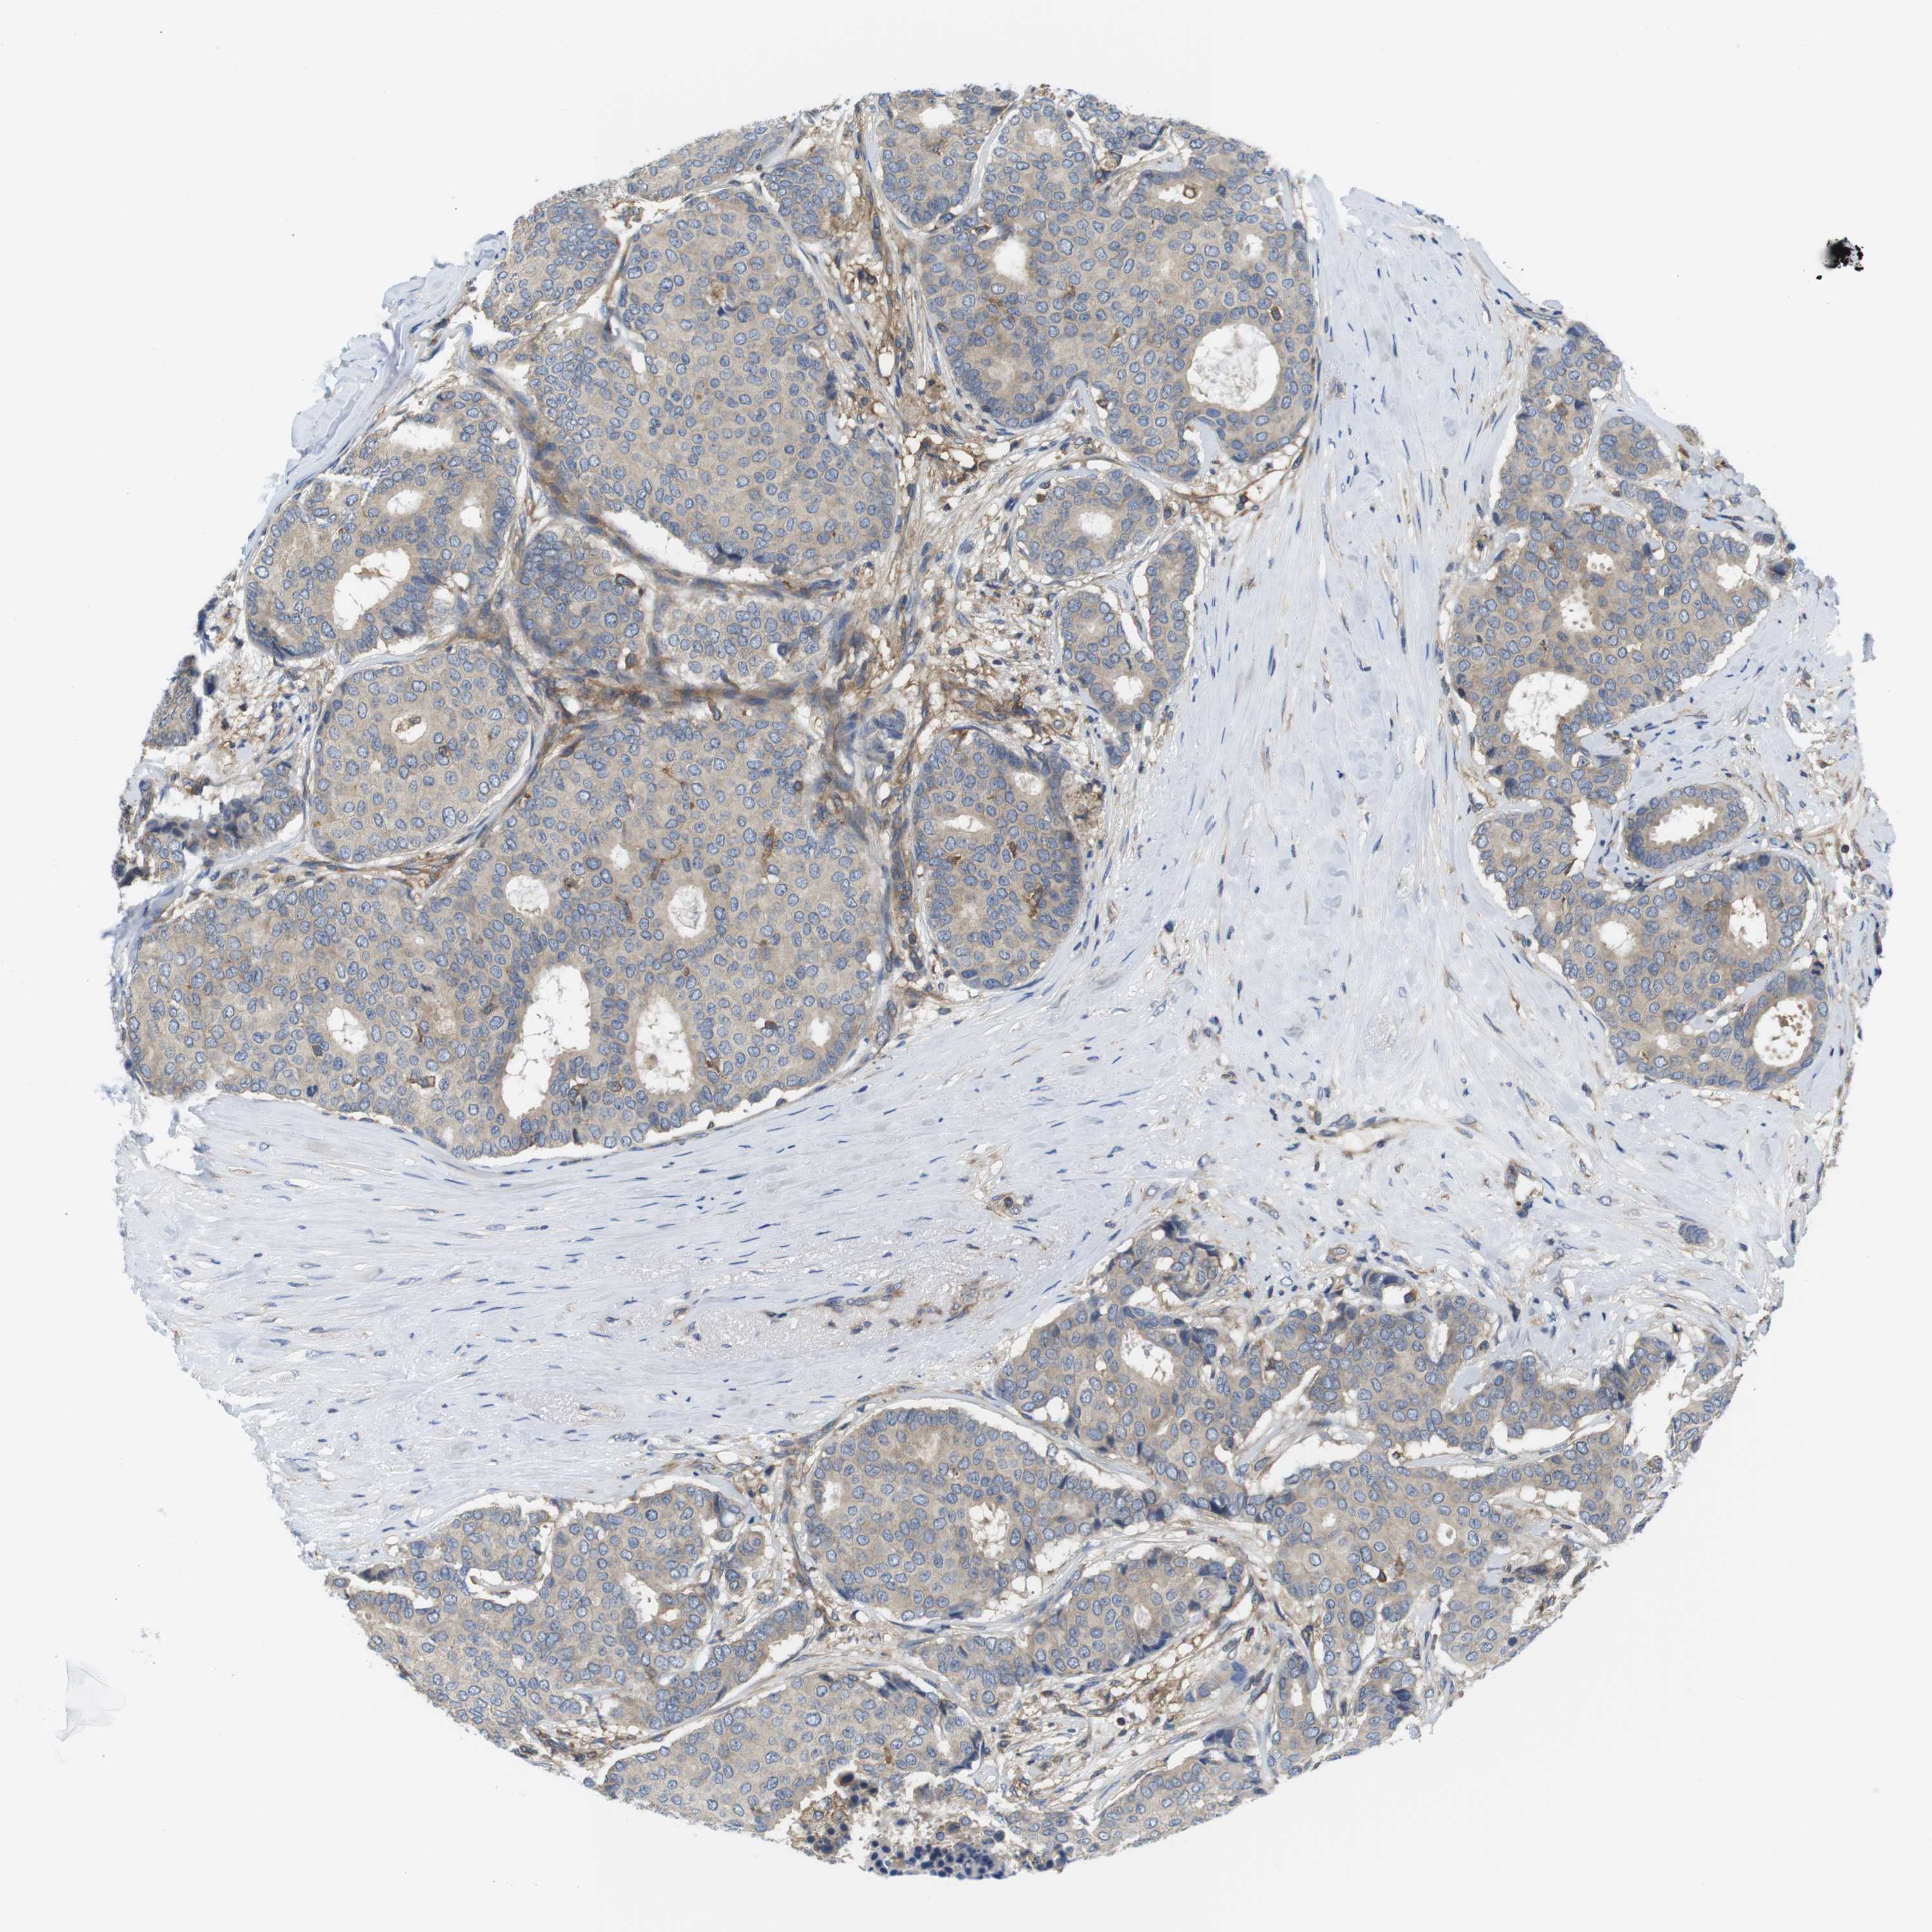

CANCER BREAST CANCER Show tissue menu

BRCA TCGA BRCA VALIDATION PROTEIN EXPRESSION